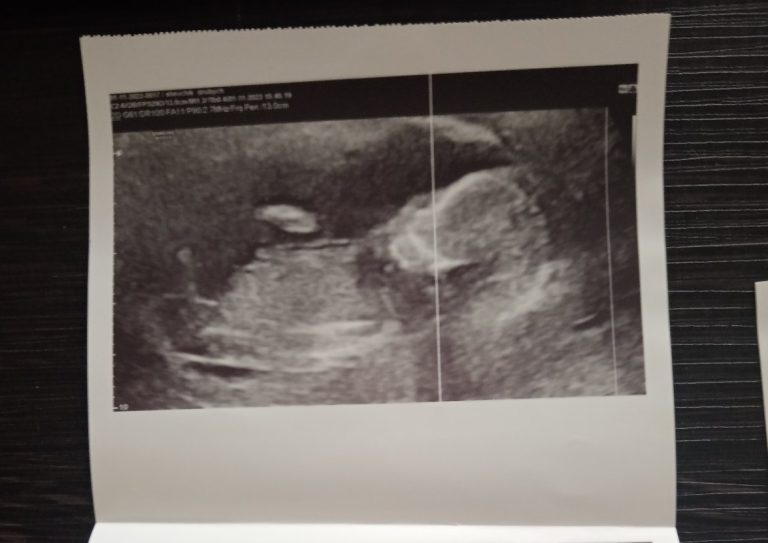

Беременность проходила сложно с первых недель. Яна жила от госпитализации до госпитализации, врачи ставили под вопросом угрозу выкидыша. Но УЗИ показывало, что все в порядке, патологий не находили. Сообщили пол малыша – девочка.

Больше всего Яна боялась, что по приезду в больницу ей сообщат страшную новость, но, слава Богу, все обошлось. Доктор успокоила и показала на мониторе во время УЗИ бьющееся сердечко ее девочки. Кровотечение остановили.